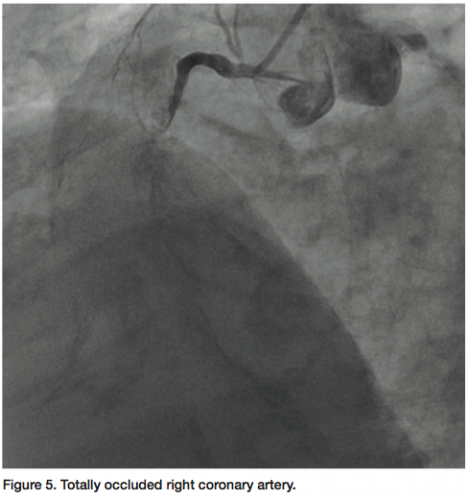

The value of FFR measurement can also be seen in a case at our facility. The patient presented with continuing chest pain on exertion. The RCA was found to

be totally occluded (probably chronic) (Figure 5) and a large posterior descending artery (PDA)/postero-lateral artery (PLA) system is noticed on angiography of the left arteries. The collaterals to the PDA/PLA appear to come from the left anterior descending coronary artery (LAD) and circumflex (Figure 6). The chronic total occlusion (CTO) appears moderate in length once the collateral and main vessels are visualized, with a calcific channel outlined.